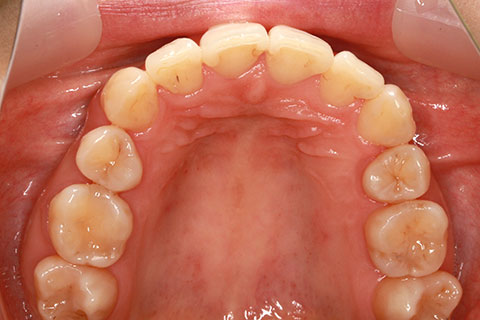

フルリンガル矯正2(上下の歯を舌側矯正で治療)

治療前

治療中

治療後

- 年齢・性別

- 42歳男性

- 治療期間

- 1年6ヶ月

- 抜歯

- なし

- 治療費

- 120万円(税込み)

- 備考

- マルチブラケットを用いた矯正治療

- 治療内容

- 反対咬合をフルリンガル矯正治療にて改善

- 施術の副作用(リスク)

- 表側矯正と比較して、歯根の角度を確立する「トルク」の力がかかりにくい。